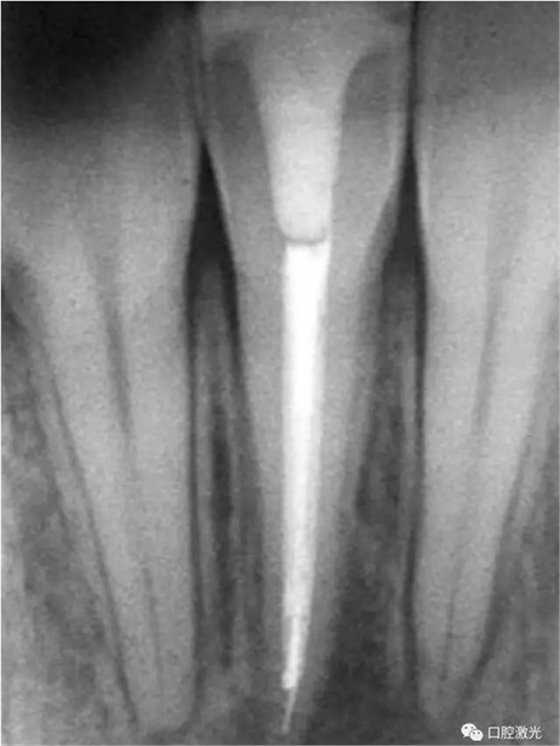

46治療前X光片

半導(dǎo)體激光治療中

6個月后治療效果